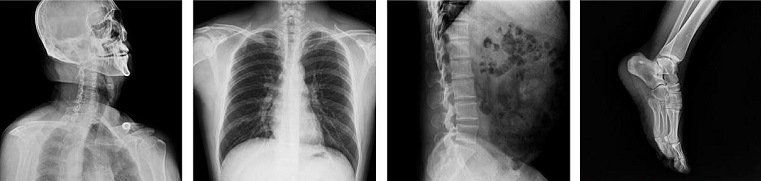

HDR-7200b.

Attrezzature X Ray.

Imaging Attrezzature diagnostiche